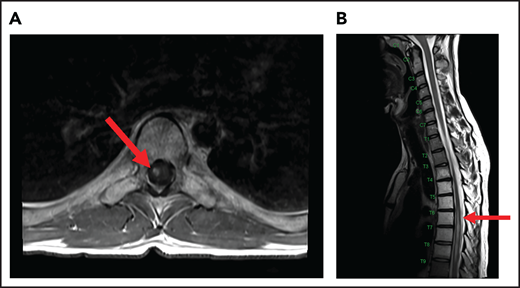

A 24-year-old man presented with stage IVB DLBCL and completed 6 cycles of R-CHOP, with FDG-PET after treatment showing resolution of all disease except in the mediastinum. After a biopsy of this residual FDG+-confirmed DLBCL, he received treatment with salvage chemotherapy with minimal response, followed by mediastinal involved field radiation therapy (IFRT) to a dose of 40 Gy plus a 6-Gy boost, after which he had a CR. Subsequently, he underwent autologous SCT followed by RIC allogeneic SCT. He remained in CR for 16 months, at which time he presented with 3 weeks of new right leg weakness, erectile dysfunction, and urinary hesitancy. The results of a brain MRI were unremarkable, but a spine MRI demonstrated spinal cord expansion and edema with multifocal enhancement within the prior radiation therapy portal from T5 to T9, demarcated by fatty marrow replacement between the T5 and T9 vertebral bodies (Figure 4). A diagnostic evaluation, including CSF analysis, was negative for malignancy, infection, autoimmune or inflammatory conditions, or demyelination. He was diagnosed with radiation-induced myelitis. He was treated with HD-MTX and had a minimal response. Treatment with bevacizumab led to complete resolution of the lesion, and after intensive physical therapy, he regained neurologic function.

MRI of the cervical and thoracic spine of a patient with radiation-induced myelopathy. (A) Axial T1-weighted image after gadolinium contrast shows enhancement within the spinal cord. (B) Sagittal T2 image shows a signal change throughout the patient’s prior radiation portal from T5 to T9, demarcated by fatty marrow replacement between the T5 and T9 vertebral bodies.

Ionizing radiation to the brain or spinal cord can cause acute, subacute, or delayed adverse effects.58 Acute brain toxicity from radiation is typically related to cerebral edema and/or raised intracranial pressure and resolves with corticosteroids. Subacute effects caused by radiation-induced necrosis occur weeks to months after radiation and usually present with headache, lethargy, and focal neurologic deficits. Rarely, radiation myelopathy can result from focal radiation delivered to the mediastinum for HL and NHL, as in case 5.61 Spine MRI typically shows contrast enhancement within the spinal cord, and symptoms may resolve with corticosteroids. Bevacizumab has been used to treat radiation necrosis, as described in our case.62 Delayed neurotoxicity typically presents years after treatment. It can present as radiation-induced vasculopathy resulting in strokes or hemorrhage, or as brain atrophy and leukoencephalopathy. Older age and concurrent use of HD-MTX increase this risk.63